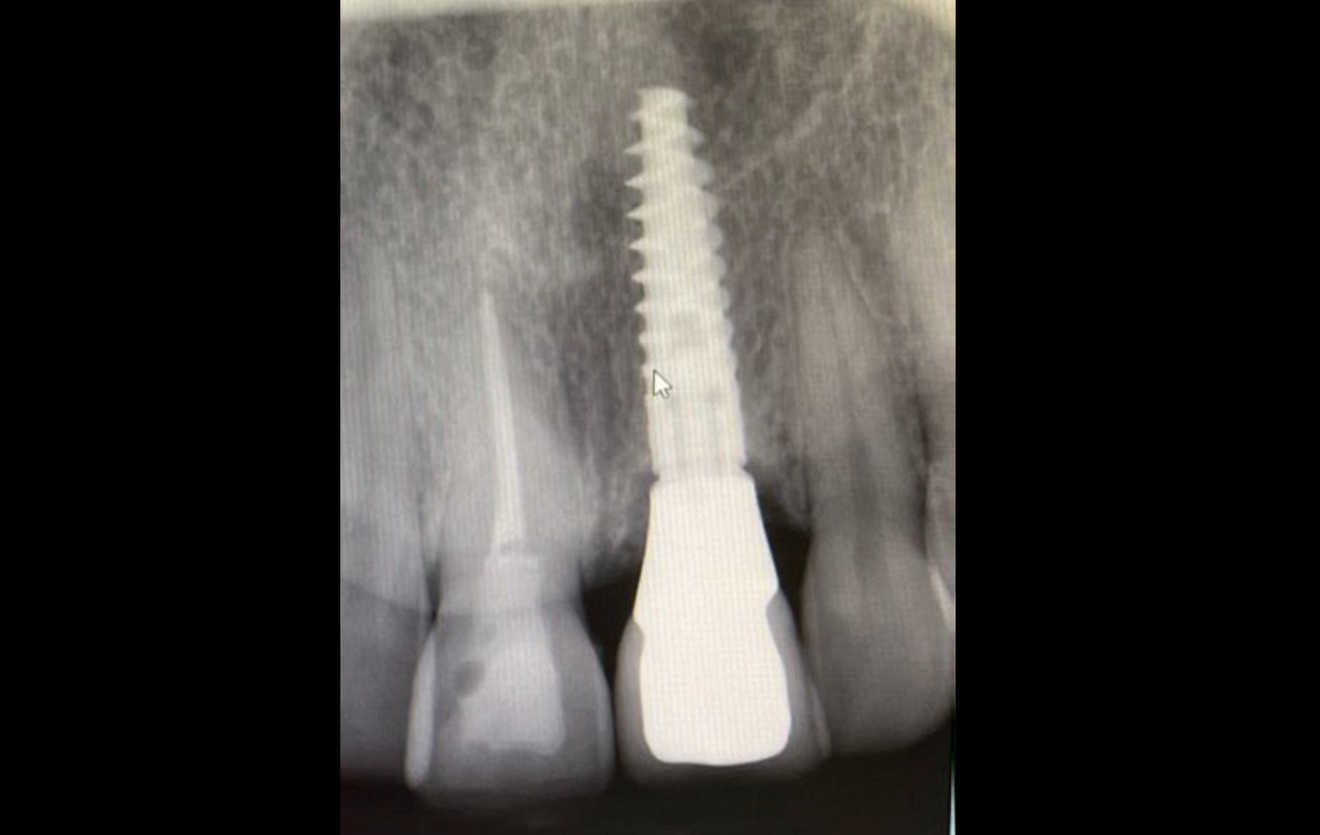

Figs. 2a–h: Demonstration of the study results through the case of a non-smoking 34-year-old female patient with a missing maxillary central incisor. Radiograph (a)...

...and clinical view at insertion of a narrow-platform 15 mm NobelActive implant (b).

Radiograph (g) ...

.. and clinical view at the seven-year follow-up (h).